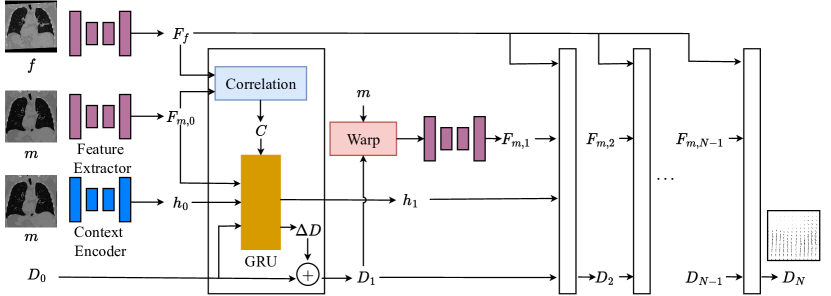

The architecture for the recurrent CNN sub-network is shown in Figure 1. Given a fixed and moving image pair ( and , respectively), the network first learns fixed and moving features ( and ) by feeding both images through a feature extractor network. A voxel-wise correlation between the fixed and moving features is computed, . Due to the large number of dimensions, the correlation is restricted so that only voxels within a certain range, of the moving voxel are considered. Additionally, the moving image is fed through a context network that extracts contextual information for the hidden network. The output of the contextual network is used as the initial hidden state of the RNN, . Finally, a displacement field with zero displacement, is initialized.

The hidden state, flow, cost volume and moving image are fed into an update block that is a modified gated recurrent unit (GRU) [14]. The GRU is almost identical in implementation to the one used by RAFT [8], and it outputs a new hidden state and a new displacement field, and . The new displacement field is used to update the aggregate displacement, i.e, . This new displacement field is used to warp the moving features (generating ), which can be used to generate a new cost volume, , for the next RNN time step. This process of updating displacement field with GRU cell and generating cost volume is repeated for RNN time steps.